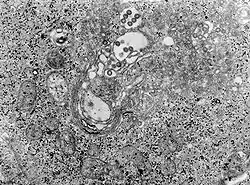

| TEM micrograph of tissue infected with Rift Valley fever virus | |